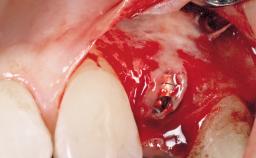

In the fall of 2003, a female patient was referred to the School of Dental Medicine, University of Geneva, for treatment of a traumatic fracture of a maxillary left lateral incisor. While at home, the patient fell down and hit a heating radiator with the anterior maxilla. During the initial examination, a week after the accident, the patient was in good general health condition and signs of pain/discomfort or clinical/radiographic infection were not observed. A moderate and localized hematoma with associated swelling persisted on the left side of the upper lip. Clinical assessment revealed a horizontal fracture at the cervical third of the anatomic crown of the maxillary left lateral incisor. In addition, a vertical crack line projecting into the cementoenamel junction (CEJ) called for a comprehensive assessment of the tooth restorability options.